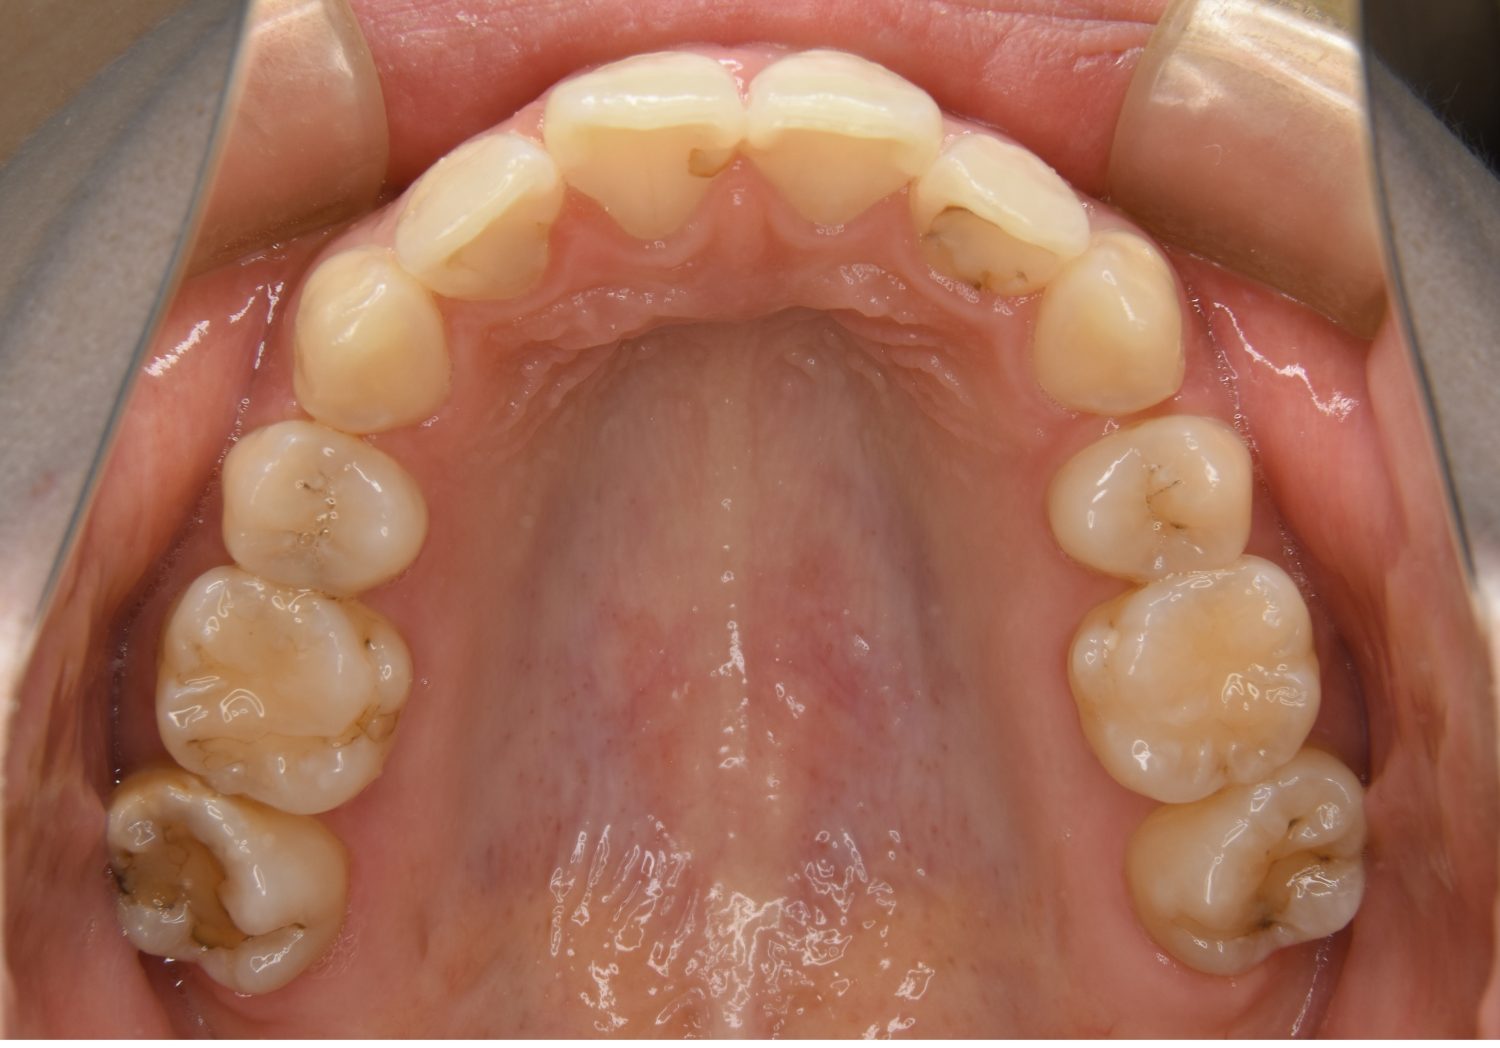

前歯部開咬の症例紹介①

Before

主訴

前歯が開いているのが気になる。

治療内容

上リンガルブラケット(舌側装置)、下ラビアルブラケット(唇側装置)に矯正用アンカースクリューを併用し非抜歯で治療を行いました。

上下の前歯が開いており前歯では全く噛めていない状態でした。臼歯の圧下を行うことで前歯でも咬合できるようになり機能面のみでなく審美面も著しく改善しました。